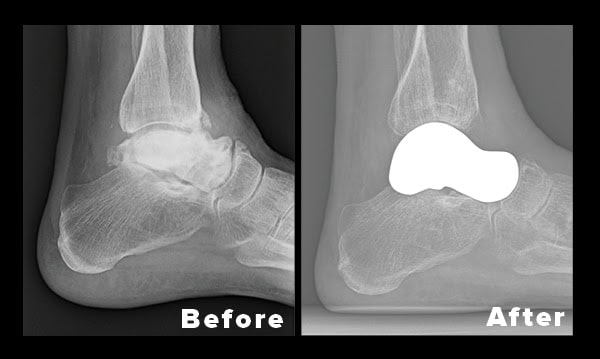

Now Performing a Total Talus Replacement with a 3D Printed Implant

New Hampshire Orthopaedic Center’s foot and ankle surgeon, Bryan A. Bean, MD is now making use of a novel 3D printing technology to custom replicate the talus bone in patients suffering from bone death known as avascular necrosis (AVN). Reconstruction of the ankle with a 3D printed replacement ensures a perfect match of the patient’s anatomy and averts the need for motion-limiting fusion surgery or amputation.

The talus bone is critical to the function of the ankle: it bears the weight of the entire body, and joins the two leg bones, the tibia and fibula, to the foot. Fractures of the talus are a common cause of AVN, which occurs when the bone dies from a lack of blood supply. However, the condition can also occur without any known cause.

The implant fabrication process begins by reversing CT images of the healthy talus bone in the patient’s opposite foot to create three implants of slightly different sizes. In this case, Dr. Bean utilized Restor3D, a company in Durham, North Carolina, to replicate the diseased bone. During surgery, the best fit is determined, and the final cobalt chrome talus is implanted.